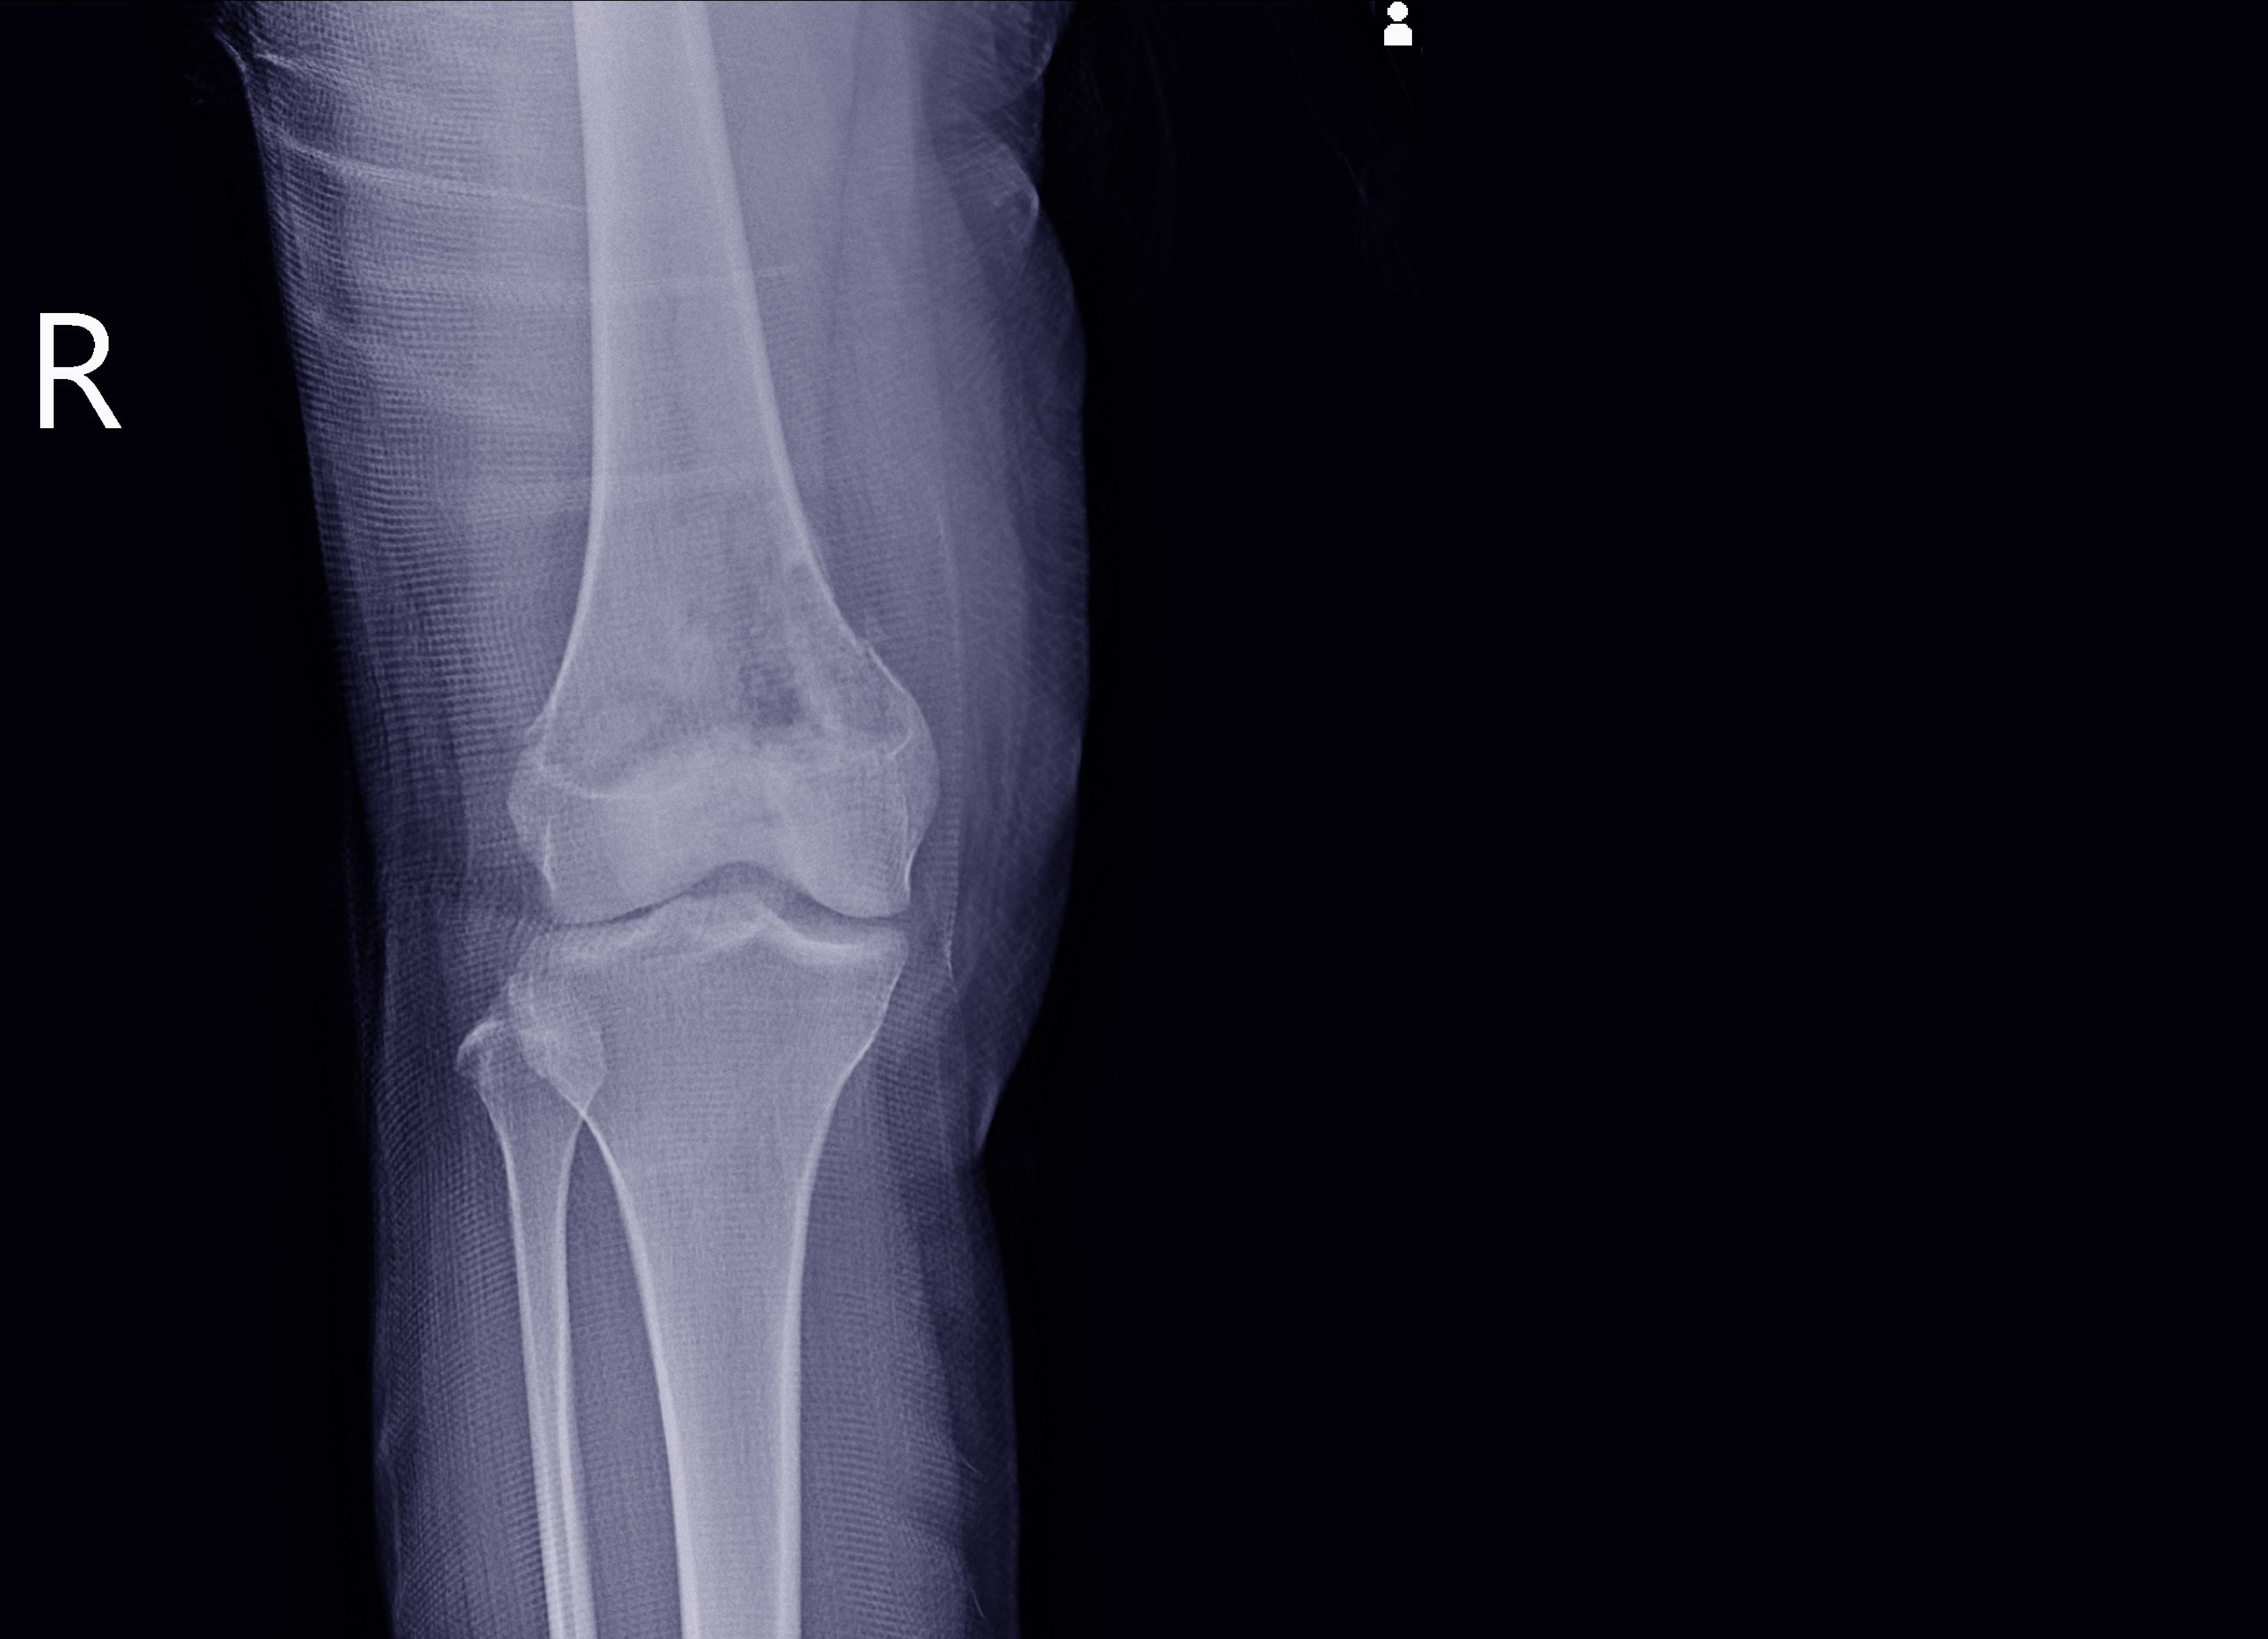

برنامج زمالة مدته عامان تم تصميمه لتوفير خبرة معمقة للأطباء الذين أتمّوا برنامج تدريب التشريح النسيجي الجراحي للأطباء المقيمين. ويركز التدريب على الجوانب العملية والأكاديمية والإدارية لممارسة التشريح النسيجي، من أجل إعداد طبيب تشريح نسيجي مؤهل بالكامل مع الاطلاع الموسّع على التخصص الفرعي للتشريح النسيجي للعظام والأنسجة الرخوية. وتقدم الإدارة خدمة فعالة للتشريح النسيجي للعظام والأنسجة الرخوية.